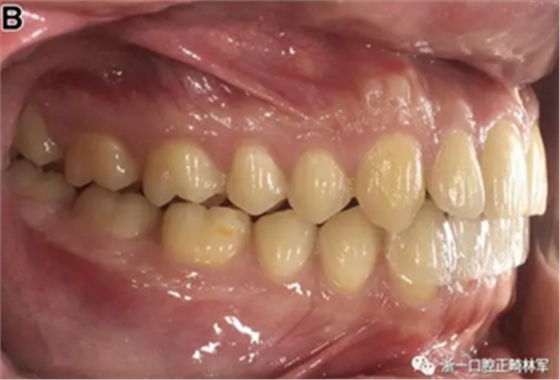

患者的上頜骨和下頜骨研究模型在最大牙尖交錯位時確定和數(shù)字化(圖2,A),作為咬合指導(咬合指導)。該數(shù)字化咬合指導在齦緣周圍進行數(shù)字化修剪,以便在CBCT掃描上可以更好得可視化(圖2,B)。

圖2. A,咬合時對象研究模型的右側(cè)舌側(cè)視圖掃描將作為未來指導;該指導稍后用于將懸浮的下頜骨配對到修剪的上頜骨;B,左側(cè)舌側(cè)視圖的數(shù)字化修整牙合引導。